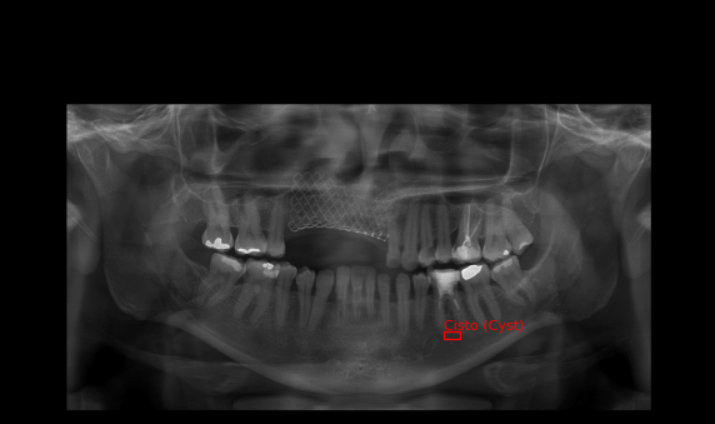

Como mostrado na imagem do dataset acima, temos três pastas chamadas: CREATML (JSON), PascalVOC (XML), YOLO (TXT) com as coordenadas dos cistos, que se mostrarmos utilizando as bibliotecas OpenCV e Matplotlib temos imagens como as ao lado.